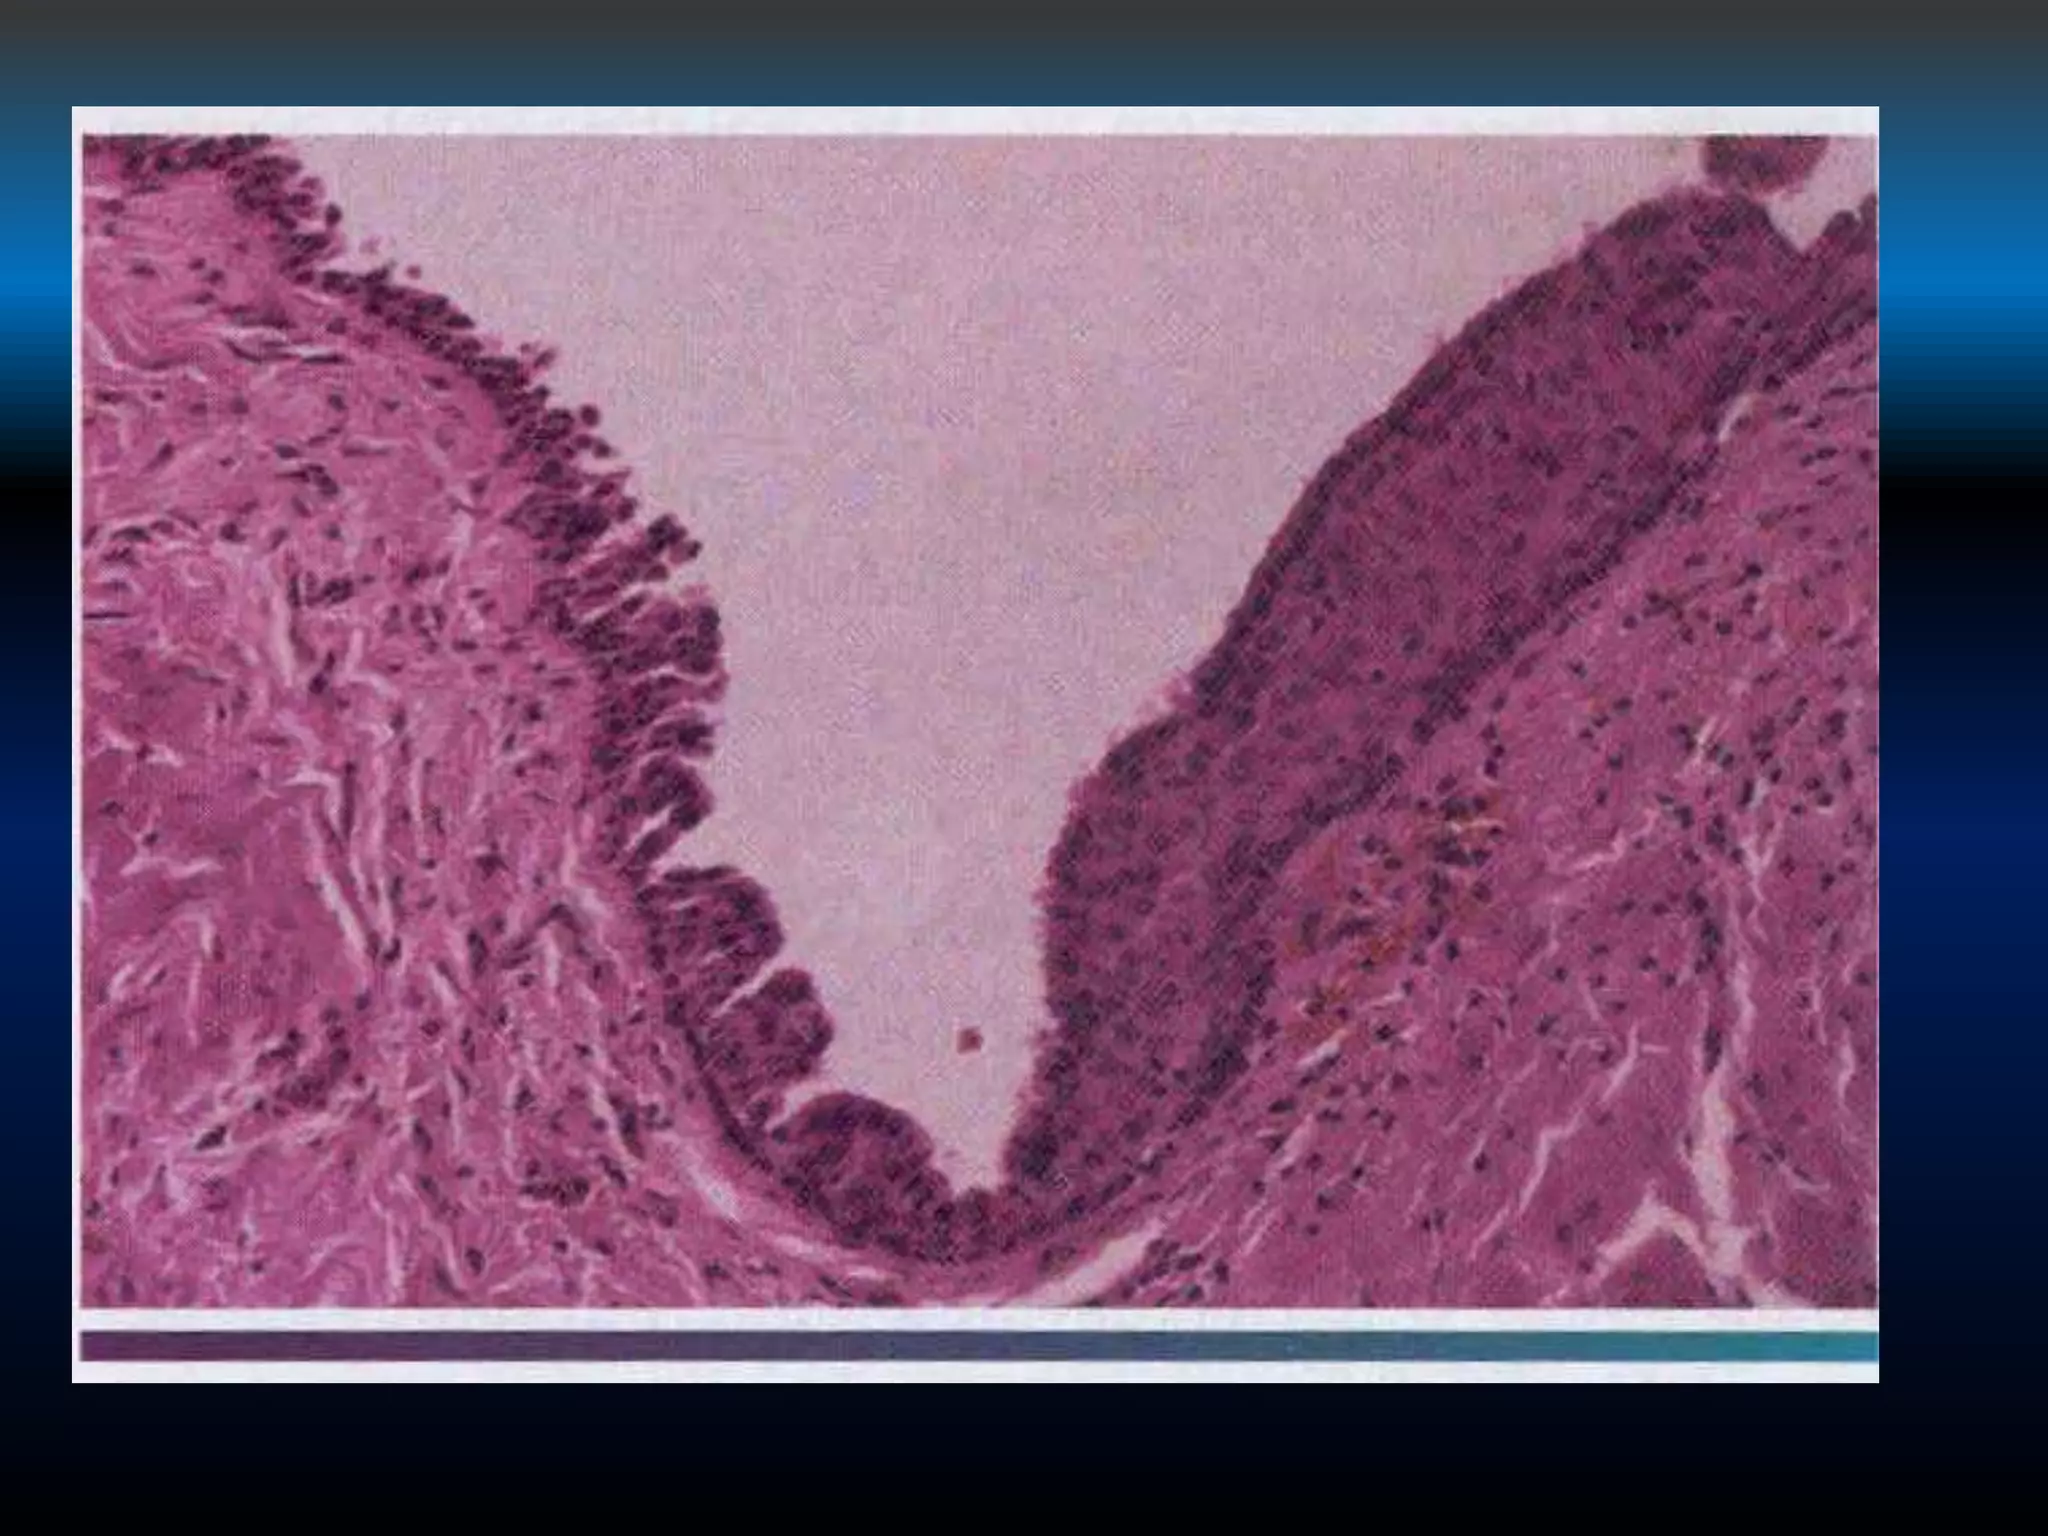

The cyst lumen is usually lined by a thin layer of

stratified squamous epithelium and contain

desquamated orthokeratin , the capsule wall is

thickened , consisting of a fibrous connective tissue

containing large numbers of well-formed lymphoid

follicles.

CERVICALLYMPHOEPITHELIAL CYST.

MEDIUM-POWERED VIEW SHOWING A CYST LINED BY STRATIFIED

SQUAMOUS EPITHELIUM. NOTE THE LYMPHOID TISSUE IN THE CYST

WALL.